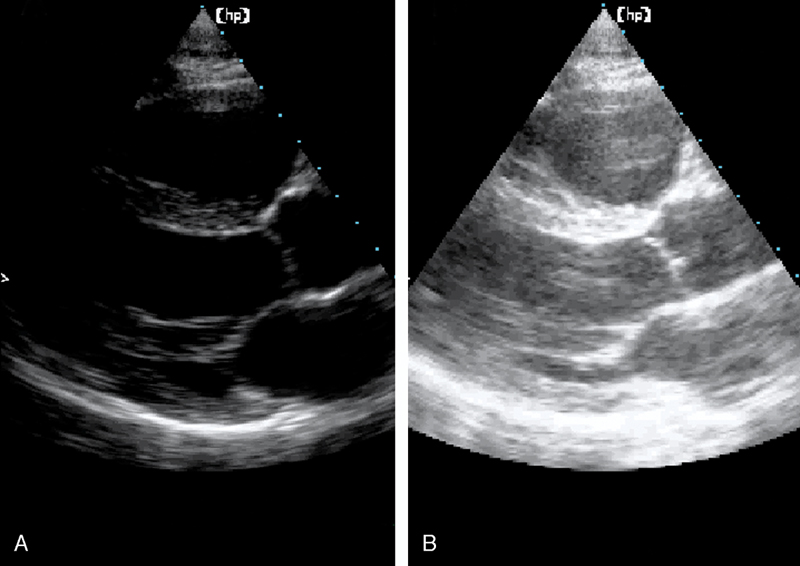

فحوصات تشخيصية لبعض امراض القلب والشرايين التاجية